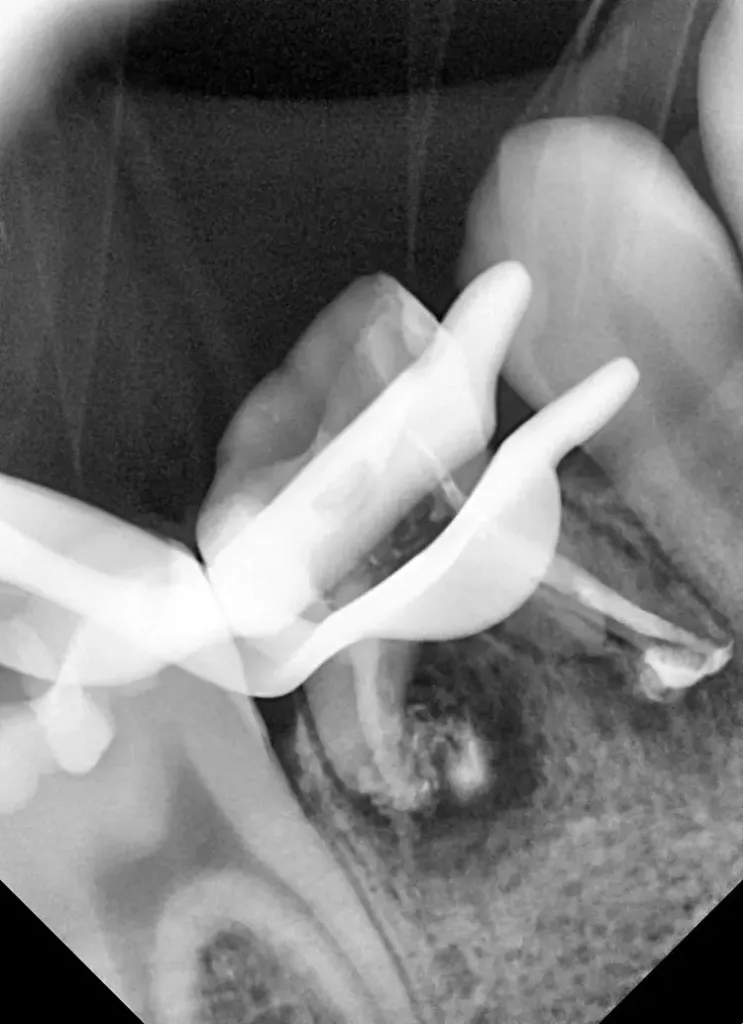

Die Länge wurde mittels Apexlocator (Propex Pixi, Dentsply Sirona, USA) ermittelt und mithilfe der Guttaperchastifte verifiziert. Nach einer finalen Spülung mit 5,25%igem NaOCl (5 ml für 2 Min.), gefolgt von 17%igem EDTA (3 ml für 1 Min.) und Kochsalzlösung (5 ml für 2 Min.), wurden die Wurzelkanäle getrocknet (Abb. 3) und mit einem hydraulischen Kalziumsilikatzement (MTA+, Cerkamed, Polen) obturiert (Abb. 2 und 4). Die finale Füllung erfolgte in derselben Sitzung mit einem fließfähigem Komposit (SDR flow+, Dentsply Sirona, USA) und Estelite ASTERIA OCE und A1B (Tokuyama, Japan) nach adhäsiver Vorbehandlung mit Optibond FL (Kerr, USA) (Abb. 5).

Aus diesem Grund erfolgte die Bestimmung der Aufbereitungslänge klassisch mithilfe einer Guttaperchaspitze (Abb. 20). Da die Wurzelkanäle sehr grazil und lang waren, konnte im vorliegenden Fall nicht so leicht mit MTA obturiert werden.